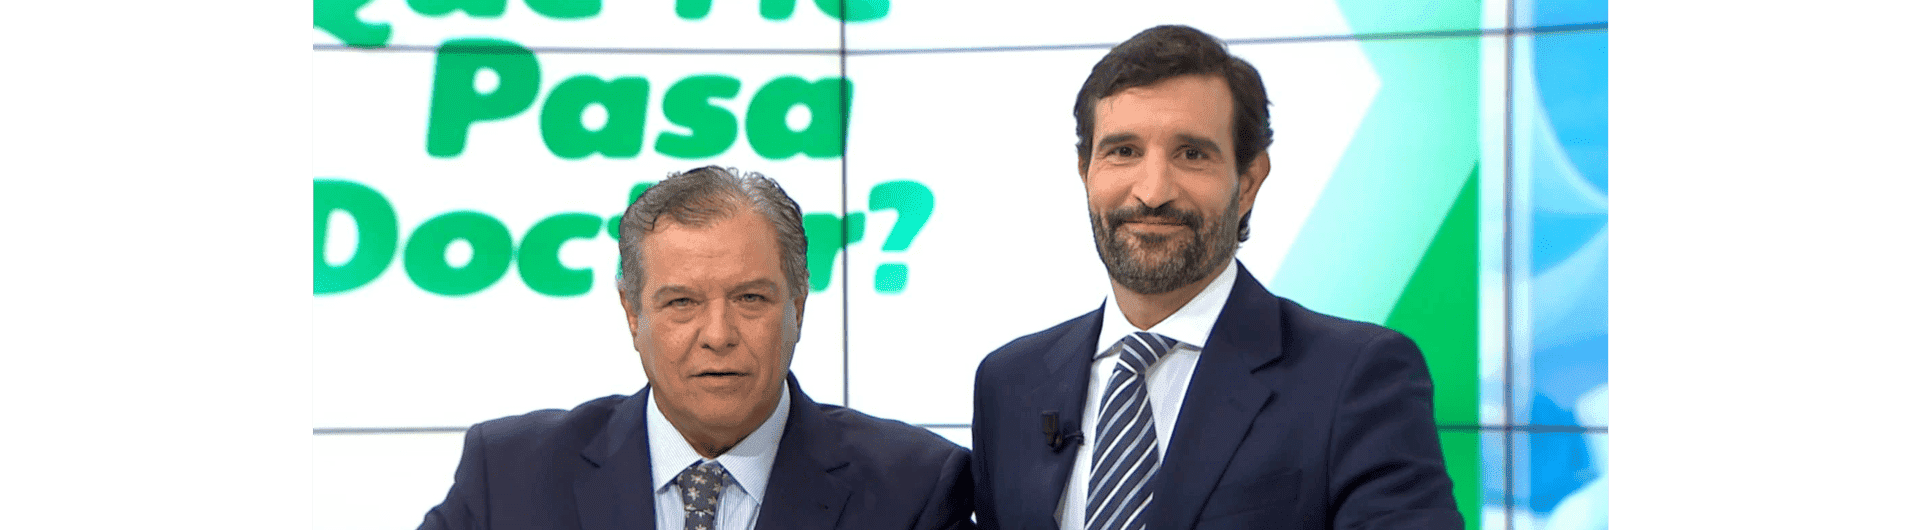

JAVIER ROMERO OTERO, DOCTOR EN MEDICINA, URÓLOGO.

Director del Departamento de Urología de HM Hospitales en Madrid y Director Médico de ROC Clinic.

La práctica clínica del Dr. Javier Romero-Otero se centra en el diagnóstico, tratamiento, investigación y docencia de la Urología relacionada con la Oncología, la Próstata, la Andrología y la Cirugía del área genital masculina. Es considerado un referente internacional en estas áreas.